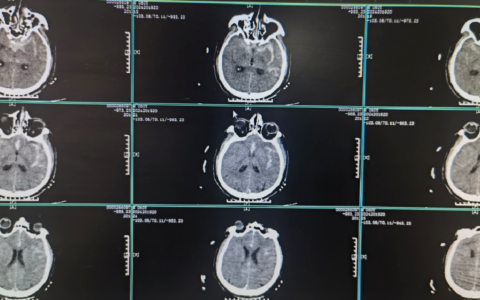

博鳌超级医院位于美丽的万泉河畔,是博鳌乐城国际医疗旅游先行区第一家开工建设、第一家建成试运营、第一家拿到国外最新上市药品在国内使用并获国家批文的综合性医疗机构。一期设置床位150张,手术室5间,其中1间杂交手术室,ICU里设置重症监护床位7张,医院配备有医学影像中心,配备有64排CT、128排CT、3.0T核磁共振等高端设备。设置有区域病理中心、区域内镜中心、检验中心、消毒供应中心、静配中心及干细胞前沿技术研究与转化中心,供先行区园区内及周围医疗机构共享高端技术平台。